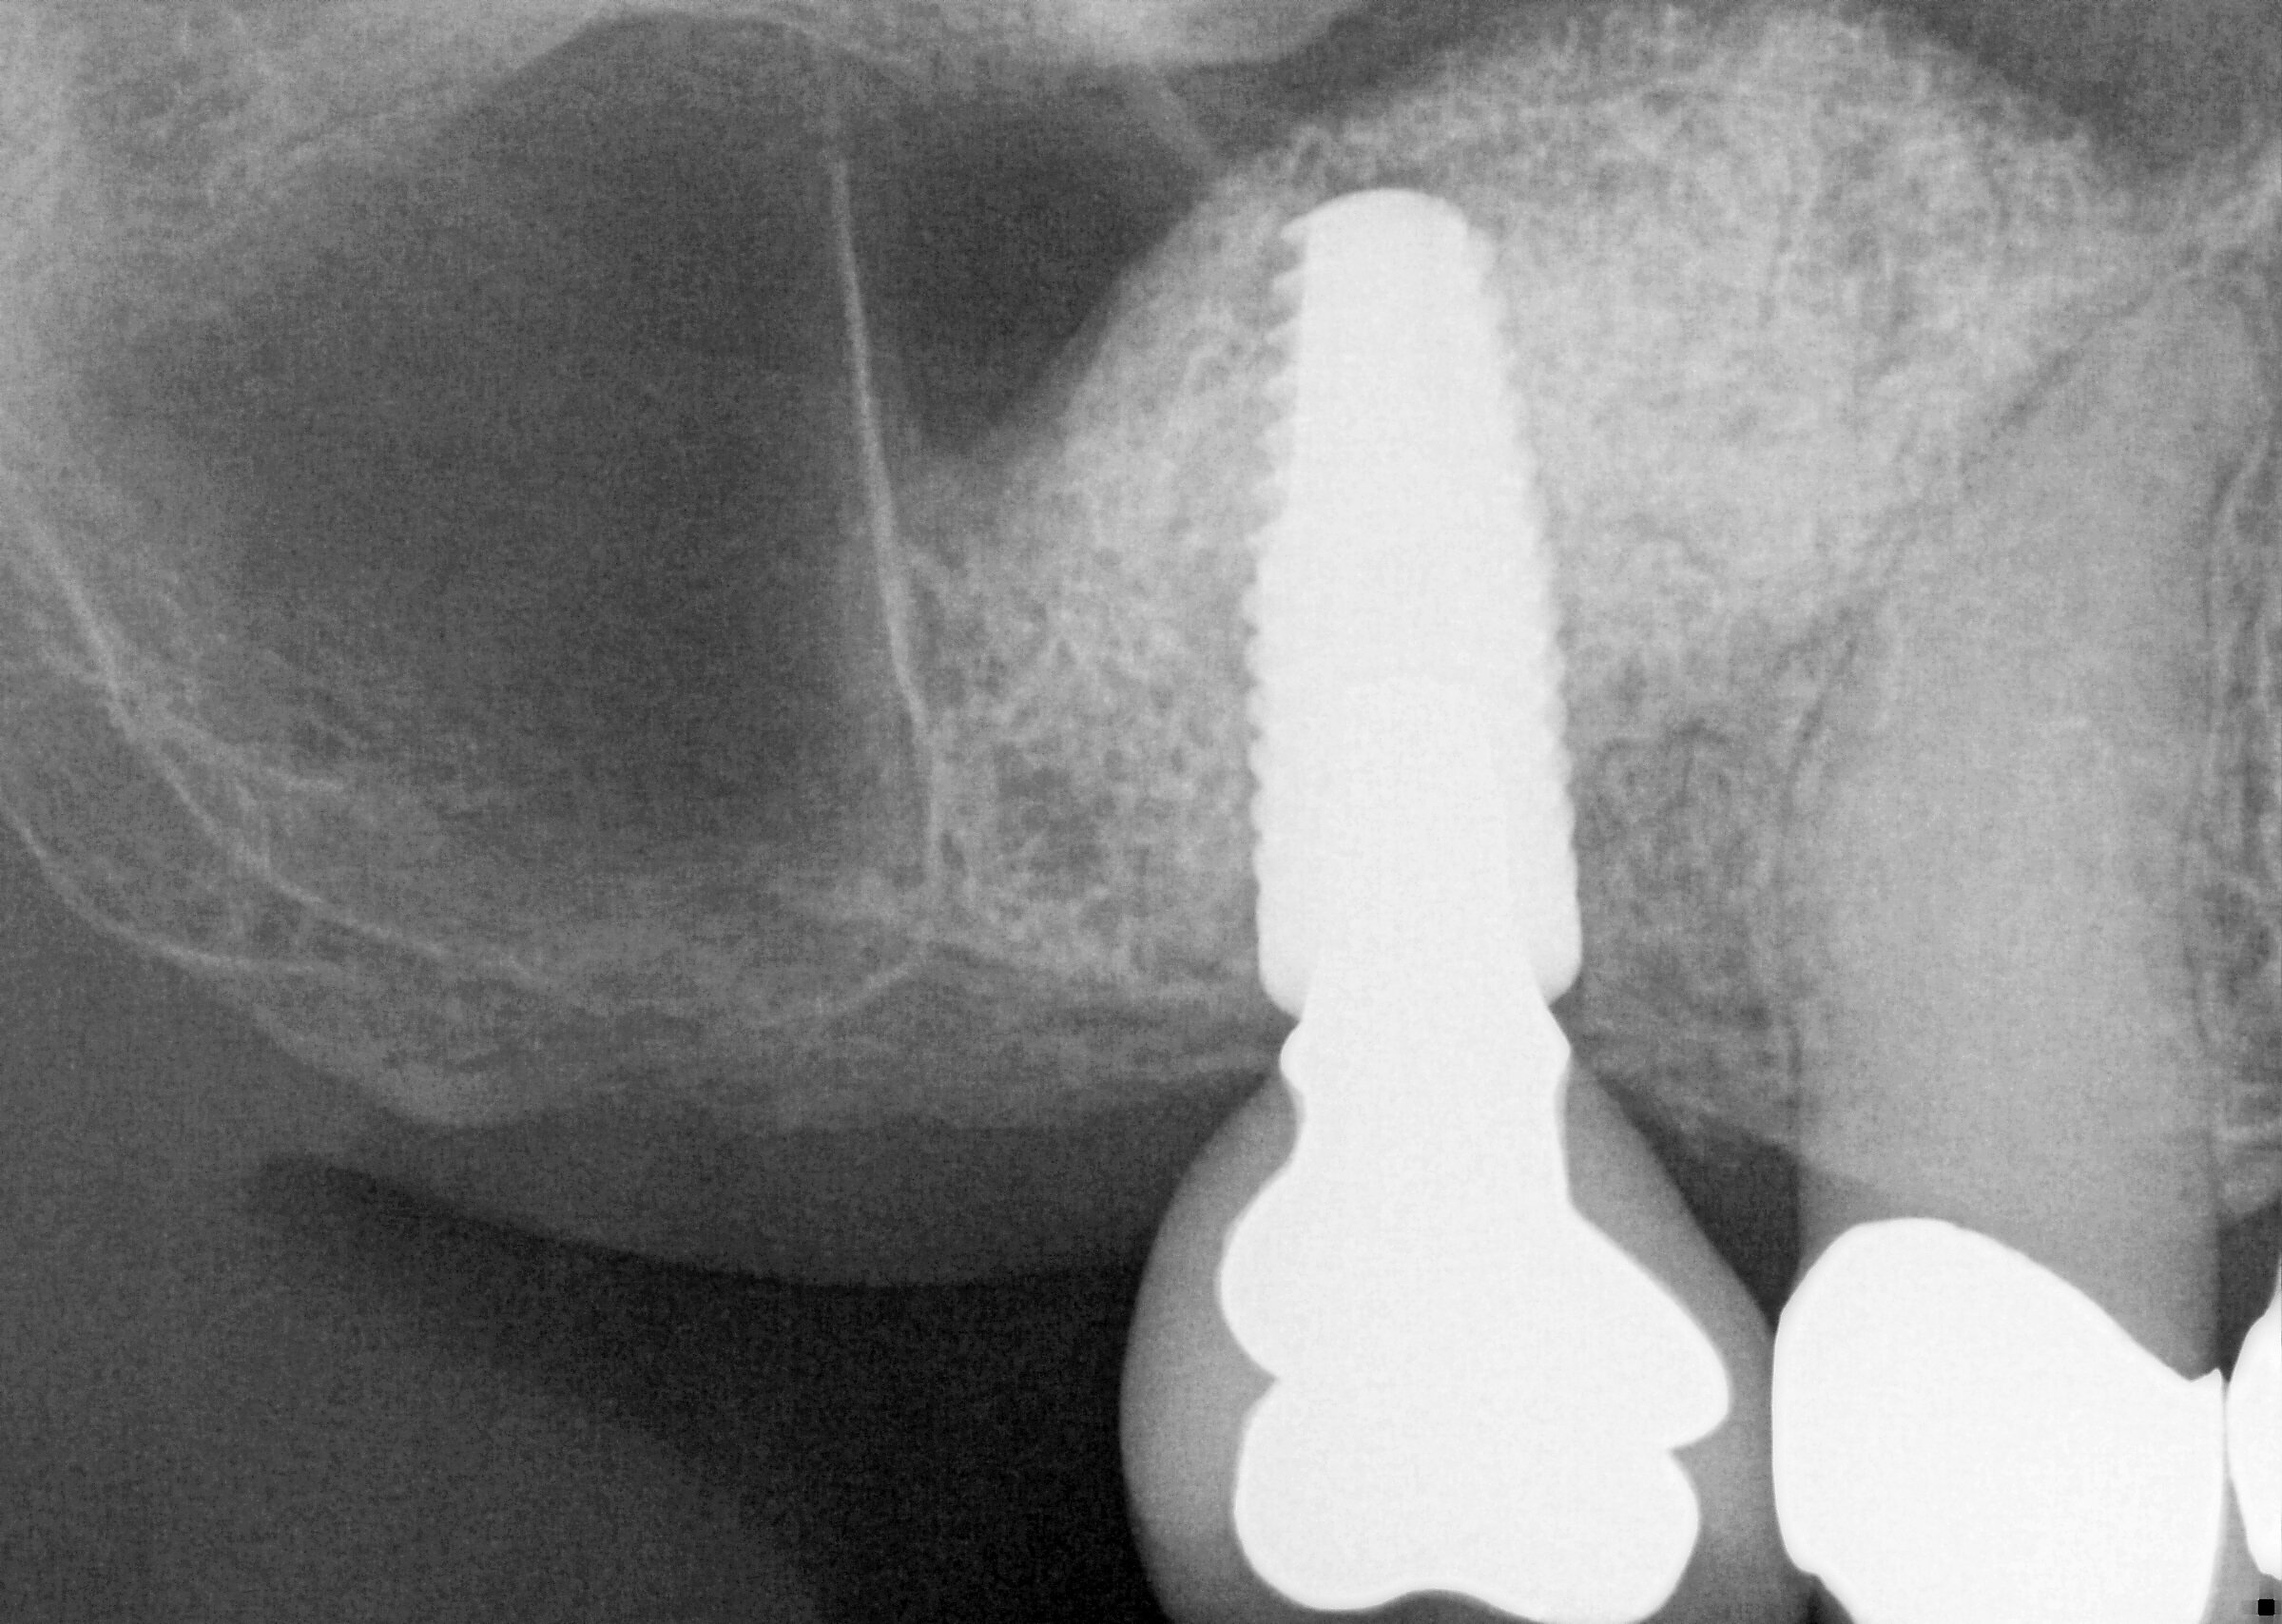

From www.boulderimplant.com

Sinus Augmentation Boulder Implants & Periodontics Periodontist Sinus Lift Expert tips for smooth sinus lift recovery journey after completing surgery. The amount of bone between the back teeth and the sinus is often limited, especially after a tooth has been lost. Over time, the sinus expands taking over the bone space around tooth roots. A “sinus lift” procedure will. It involves “lifting” the sinus membrane to make more room. Periodontist Sinus Lift.